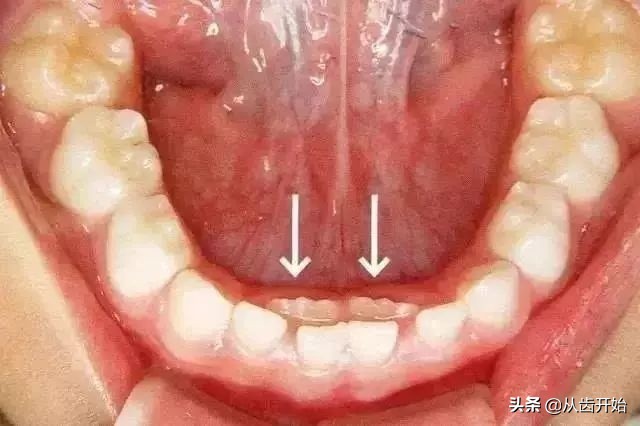

如果孩子的恒牙已经萌出,乳牙却“不肯”脱落,就叫做乳牙滞留。

主要原因:★ 恒牙胚错位 ★ 过于精细化食物减少了摩擦力导致萌出力量不足 ★ 恒牙胚先天缺失

解决方法:

尽早带孩子去做口腔检查,以确定原因。

适当恢复原该有的摩擦力(例如:吃苹果等水果时,让孩子主动去啃,而不是家人提前将苹果切小块,间接的减少了对牙齿萌出有利的刺激力量。)

恒牙已萌出而乳牙仍未脱落的滞留牙,应尽早拔除,以免影响恒牙在正常位置上萌出。

超过换牙年龄而乳牙未脱落,恒牙未萌出者,则不要轻易拔掉,若是恒牙先天性缺失,应尽量保持乳牙。